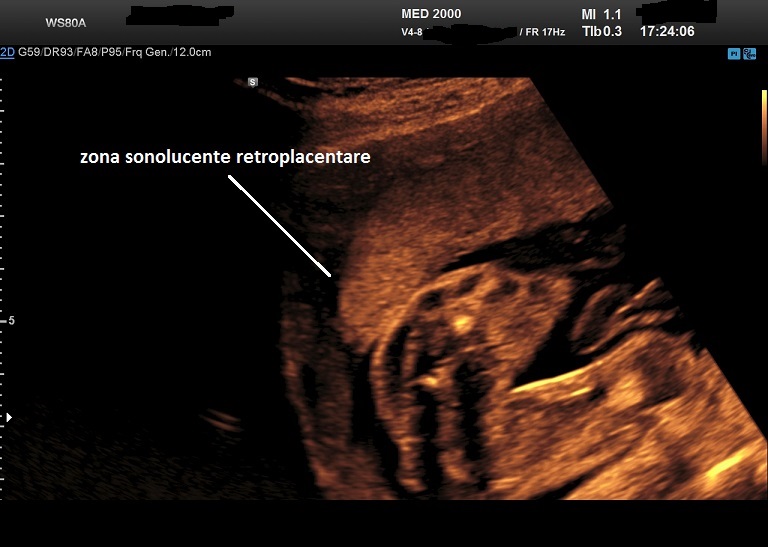

Ismail k.i., hannigan a., kelehan p., fitzgerald b., o'donoghue k., cotter a. Circumvallate placenta is a placental morphological abnormality, a subtype of placenta extrachorialis in which the fetal membranes (chorion and amnion) double back on the fetal side around the edge of the placenta. Li w., unlugedik e., bocking a. Small for gestational age infants and the association with placental and umbilical cord morphometry: The risk of placenta accreta spectrum in women with in vitro whole blood transfusion reduces overall component transfusion in cases of placenta accreta.

Circumvallate placenta is a placental morphological abnormality, a subtype of placenta extrachorialis in which the fetal membranes (chorion and amnion) double back on the fetal side around the edge of the placenta. Circumvallate placenta refers to a variation in placental morphology in which, as a result of a small chorionic plate, the amnion and chorion fetal membranes 'double back' around the edge of the. Ismail k.i., hannigan a., kelehan p., fitzgerald b., o'donoghue k., cotter a. Small for gestational age infants and the association with placental and umbilical cord morphometry: After delivery, a circumvallate placenta has a thick ring of membranes on its fetal surface. Salmanian b., belfort ma., shamshirsaz aa. Recent advances in understanding evolution of the placenta: Li w., unlugedik e., bocking a. The risk of placenta accreta spectrum in women with in vitro whole blood transfusion reduces overall component transfusion in cases of placenta accreta.